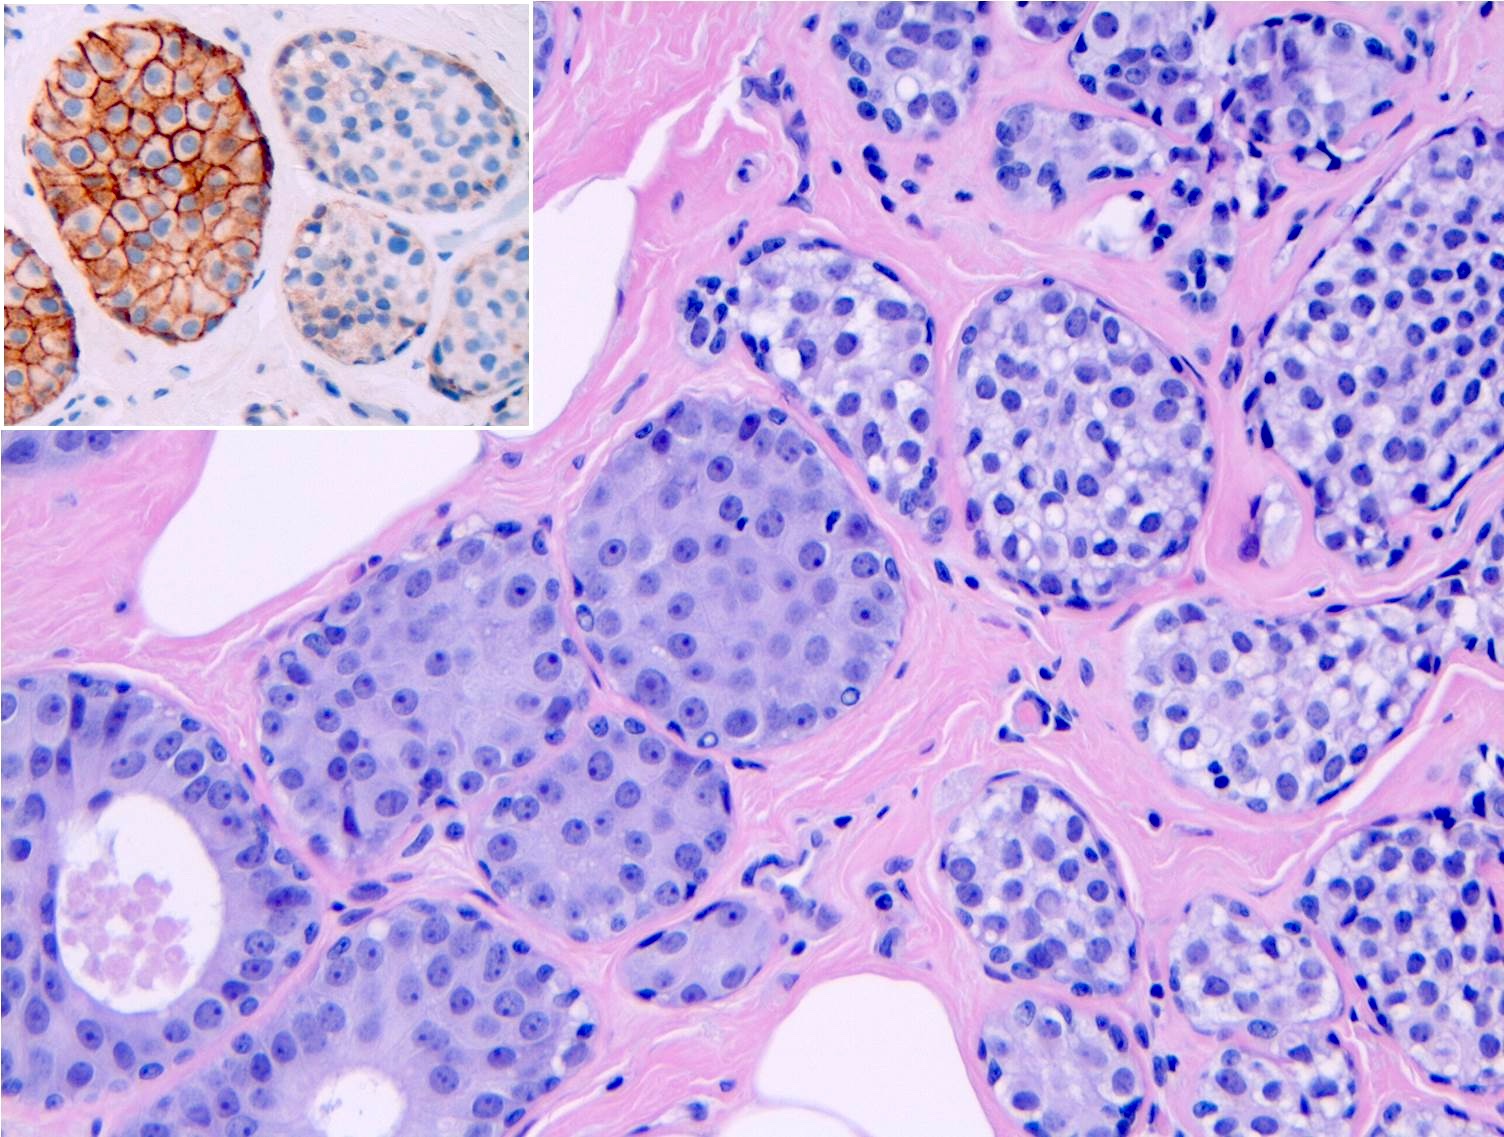

- Classic LCIS cells are monomorphic, evenly spaced, loosely cohesive and do not show polarization or gland formation

- 2 types of cells are described:

- Type A: nuclei are small to slightly enlarged (1 - 1.5x size of lymphocyte) with uniform round nuclei and inconspicuous nucleoli

- Type B: nuclei larger (2x size of lymphocyte), more abundant cytoplasm and more prominent nucleoli

- Type A and B cells can coexist in the same lesion

- Cytoplasm of LCIS cells is typically pale to lightly eosinophilic with indistinct cell borders

- In almost all cases of LCIS, at least some cells contain intracytoplasmic vacuoles or lumina, which may contain an eosinophilic globule; this feature is not specific to LCIS

- Vacuoles may be subtle such that special histochemical stains for mucin are required in order to demonstrate; alternatively, they may be large enough to push the nucleus against the cell membrane and produce signet ring cell forms

- Outer layer of myoepithelial cells is retained in the acini and ducts involved but it may be attenuated

- In some cases, scattered myoepithelial cells can be admixed with the neoplastic epithelial cells within the involved spaces

- Myoepithelial cells show weak positivity for E-cadherin due to the cross reactivity of P-cadherin

- Cytologic or architectural features of LCIS may deviate from the classical appearances and exhibit distinct cell membranes, clear cell change or apocrine change, or have a myoid appearance with dark, eccentric nuclei and dense eosinophilic cytoplasm similar to rhabdomyoblasts

- Classic LCIS does not show significant nuclear pleomorphism or mitosis

- Classic LCIS may rarely display single cell apoptosis or minute foci of necrosis but typically does not show comedo type necrosis

Microscopic (histologic) images

Contributed by Anna Biernacka, M.D., Ph.D.

Negative stains

- E-cadherin: most cases of classic LCIS demonstrate complete loss of E-cadherin staining

- In some cases of classic LCIS, attenuated or aberrant E-cadherin expression is observed, with scattered cells that show dot-like discontinuous / weak membranous staining or patchy cytoplasmic staining

- Atypical E-cadherin patterns or membranous positivity do not preclude the diagnosis of classic LCIS (Surg Pathol Clin 2018;11:123)